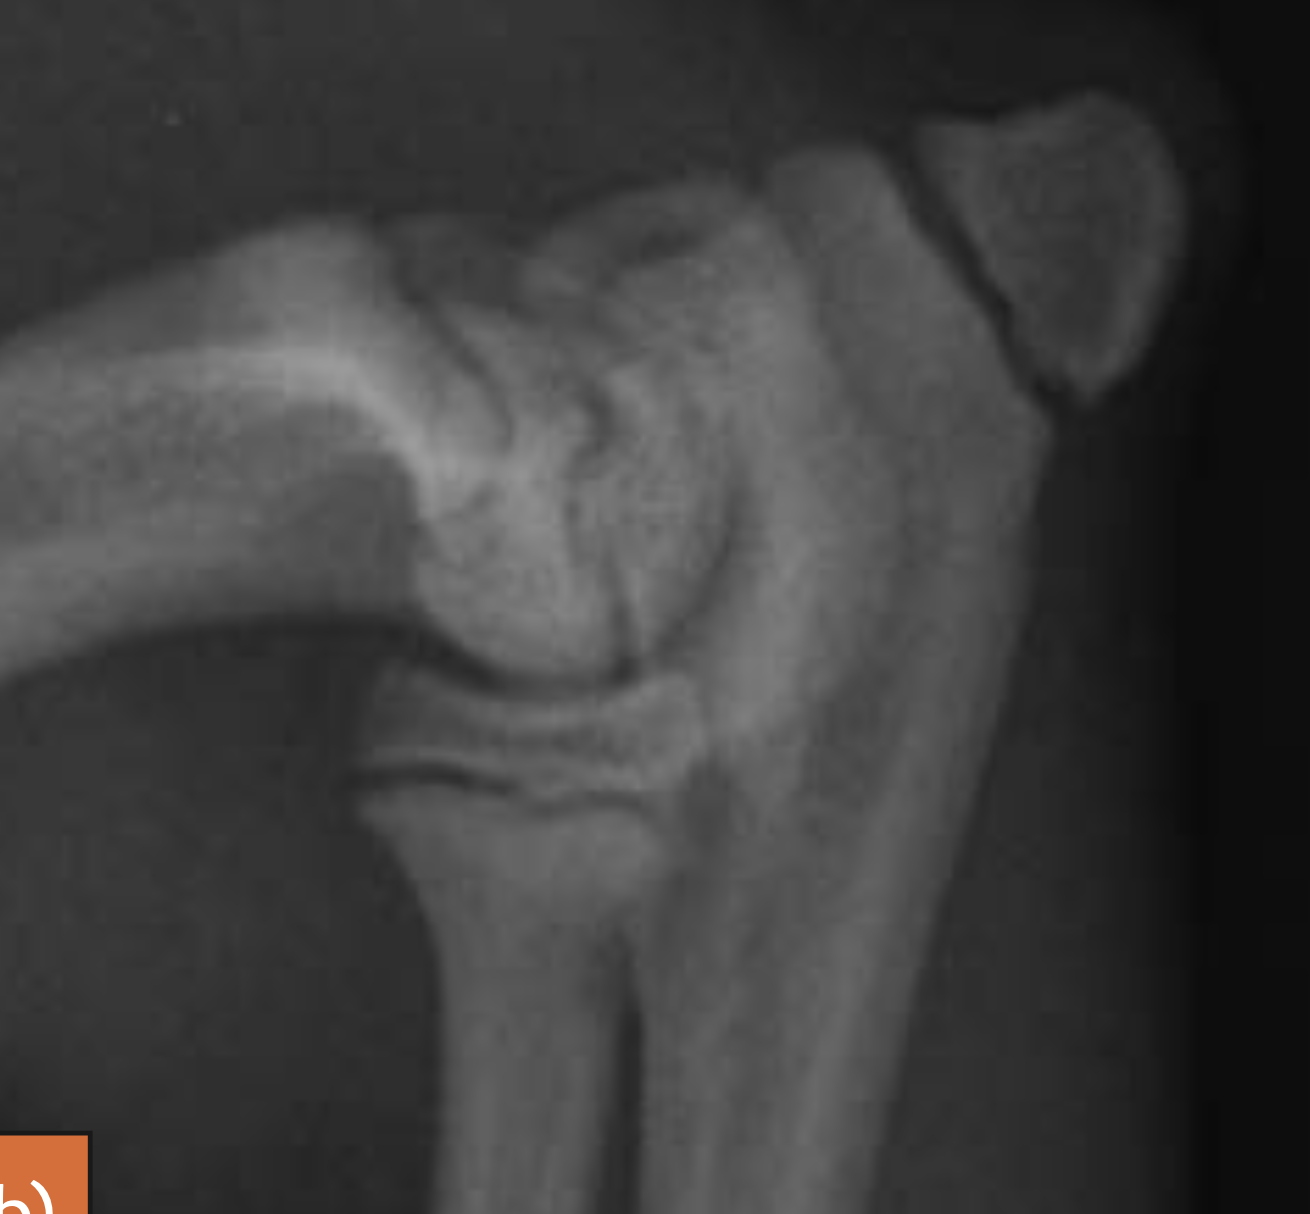

Q

Avulsed olecranon (fracture)